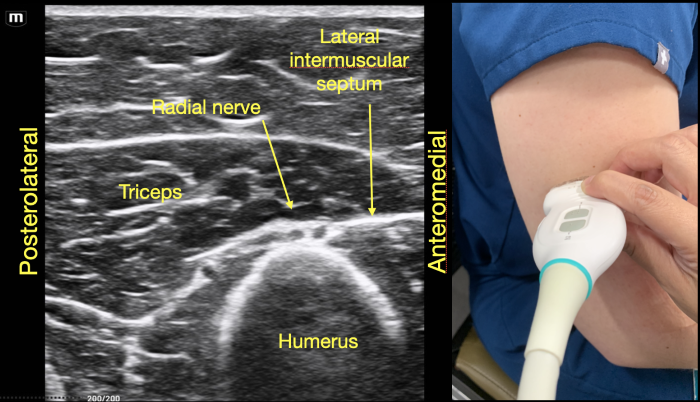

To identify the radial nerve in the mid-humerus position, have the patient in a seated position with the arm extended or held over the abdomen with the elbow flexed. Start with the probe placed transverse across the posterolateral mid-humerus and identify the radial nerve as a hyperechoic honeycombed structure lying directly on top of the humerus. At this point the radial nerve lies within the spiral groove and is also seen adjacent to the deep brachial artery. (Figure 7A)

As the probe is moved distally along the spiral groove, the posterior cutaneous nerve of the forearm can be seen branching from the radial nerve just prior to the lateral intermuscular septum (Figure 7D). In Video Clip 1, the radial nerve passes from the triceps into the biceps through the linear echogenic lateral intermuscular septum, which is a hyperechoic connective tissue layer separating the dorsal and anterior compartment of the arm.13